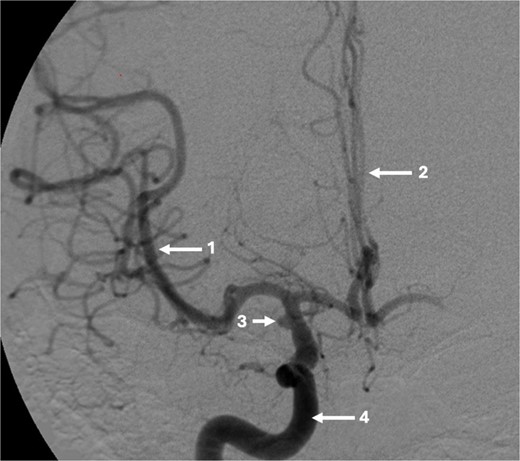

A 43-year-old lady, with known hypertension, presented with severe and sudden onset headache in 2010. Initial computed tomography (CT) head confirmed a diffuse subarachnoid haemorrhage (images not available) and a subsequent CT angiogram showed a right supraclinoid internal carotid artery (ICA) aneurysm (Fig. 1). CT Angiogram also showed an unruptured left posterior communicating which was thought not to be related to this patient’s presentation and managed conservatively with serial imaging. The patient underwent emergency craniotomy on the same day where an encircling Sundt clip was applied to secure the aneurysm. She made a full neurological recovery and was discharged from hospital. Post-operative day 1 CT angiogram demonstrated relatively normal calibre of the right A1 portion of anterior cerebral artery (ACA) and M1 portion of middle cerebral artery (MCA), in the terminal carotid region (Fig. 2).

Pre-operative CT angiogram demonstrates normal appearances of the (1) MCA, (2) ACA with, (3) laterally projecting terminal carotid sidewall aneurysm. (4) R ICA.